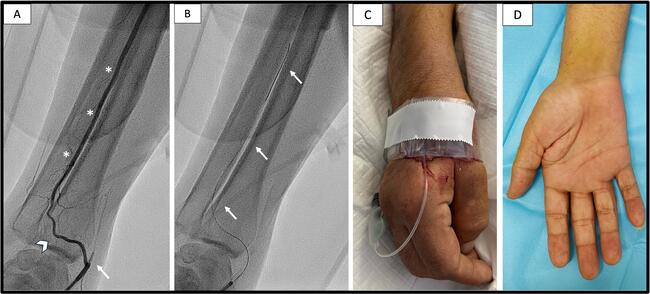

Doppler ultrasound detected flow in the right distal radial artery (dRA), which was chosen as the access site. A 6-French (Fr) sheath was used to cannulate the dRA but was advanced up to the mid-part because of resistance. Contrast injection depicted radial artery occlusion (RAO) and patent carpal branches to the interosseous artery (IOA) (Figure A, Video 1). After administration of the spasmolytic cocktail (2500 IU heparin, 2.5 mg verapamil, 200 μcg nitrates), a 0.014-inch coronary wire failed to cross the RAO through a 6-Fr Judkins Right 4 (JR4) catheter. The coronary wire was redirected to the carpal branch, which served as a collateral channel for placing the wire in the IOA (Figure B, Video 2). A 4-Fr JR4 catheter was advanced to the IOA and the 0.014-inch wire was exchanged for the J-tip 0.035-inch wire. To prevent catheter-induced ischemia of the forearm, we used 4-Fr diagnostic catheters in the IOA to allow adequate blood supply to the palm and fingers. CA revealed patent left circumflex and in-stent chronic total occlusions of all other coronary arteries. Hemostasis was achieved with the application of a TR Band (Terumo) (Figure C).

The clinical course was uneventful (Figure D), and the patient was referred for bypass surgery. In cases of radial artery occlusion, accessing the IOA through the dRA provides a safe and effective approach to the central arterial tree.